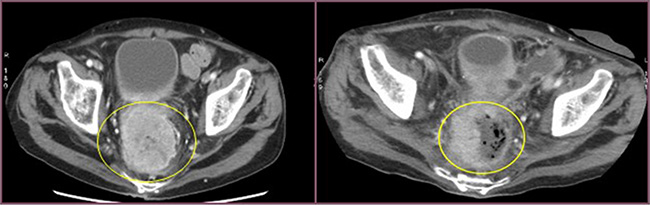

All patients experienced local disease control; in 4/12 cases (33%) we observed an outstanding radiological response with a dramatic reduction in the tumor size which led us to radical surgical resection. (Figures 1, 2, 3). Main result of the volume change is summarized in the Table 2. The Only patient who required DEBIRI twice achievied stable disease.

Figure 1: Cross section of contrast enhanced CT scan of the pelvis (venous phase). Left image: into the yellow circle tumor before chemoembolisation. Right image: into the yellow circle the reduction size of the lesion (30 day after treatment).